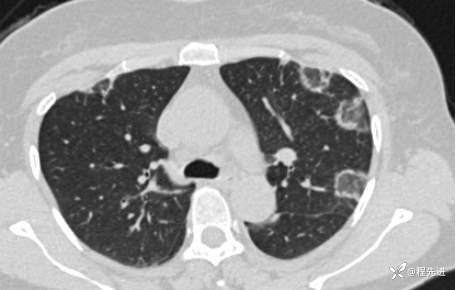

【心胸】特别精彩病例|胸闷1月余,好漂亮的反晕征呀

患者性别:女

患者年龄:57岁

简要病史:胸闷1月余

抗中性粒细胞胞质抗体相关性血管炎 (15)